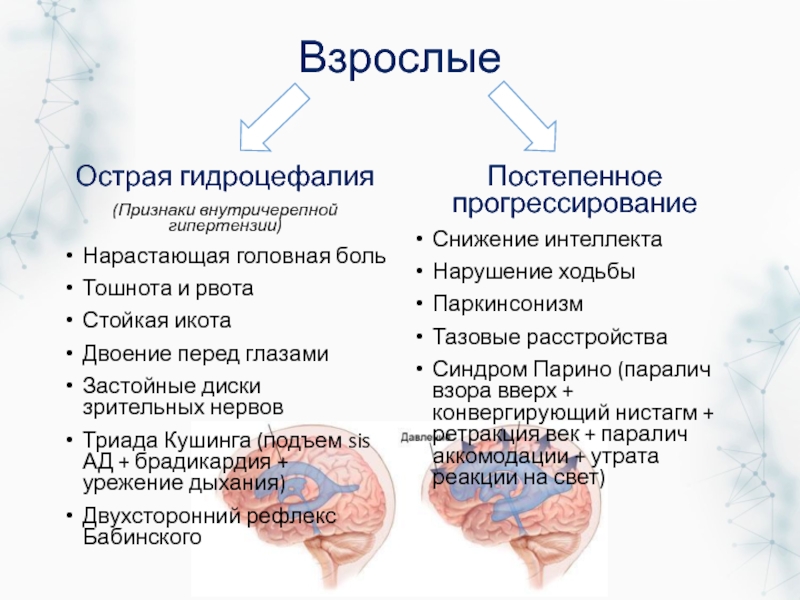

Признаки умеренно выраженной наружная

Признаки умеренно выраженной наружная 113 фото